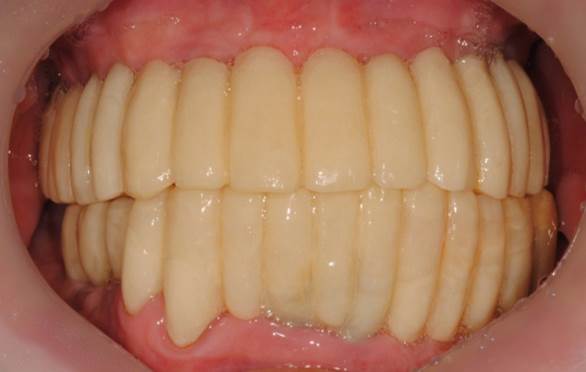

“AnyRidge shows excellent esthetic results

with Zirconia prosthesis in full-mouth rehabilitation case . ”

Clinical case: AFull transition from natural teeth to all-on-6 bridges

with AnyRidge implants

- Courtesy of Dr. Rabih Abi Nader, UAE -